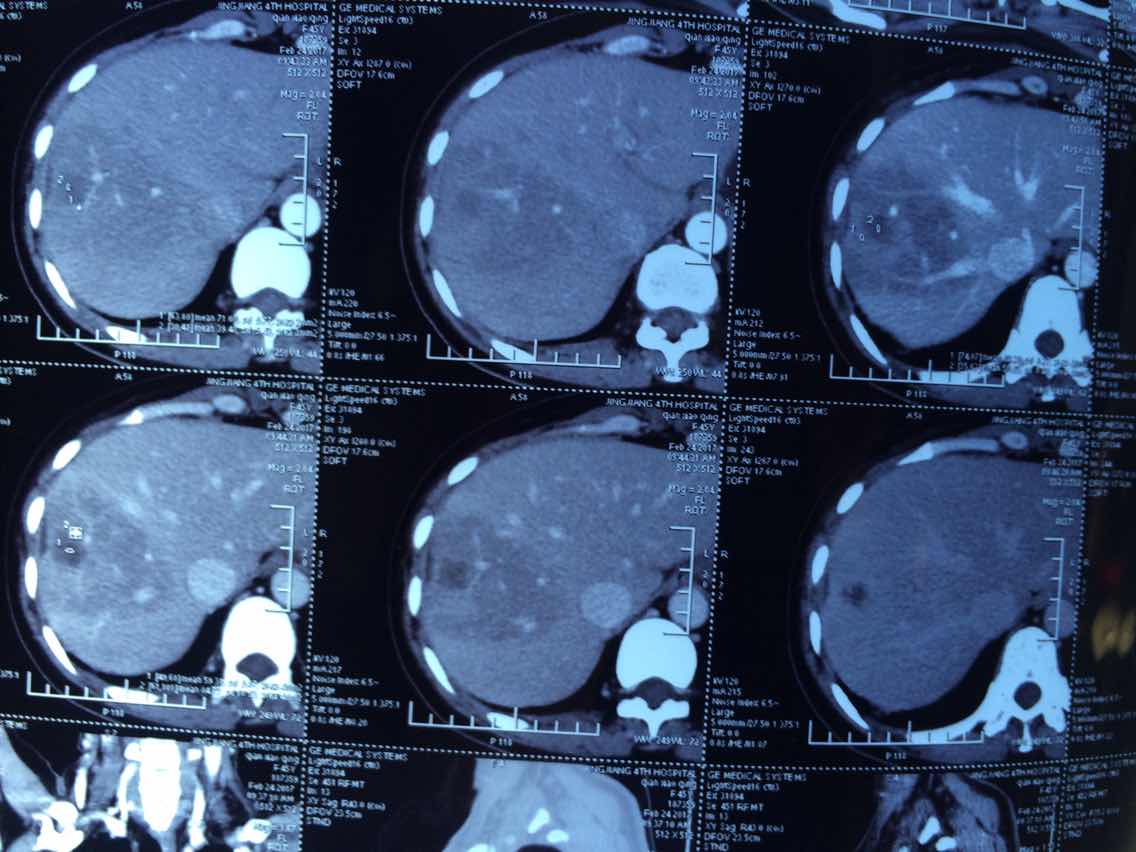

2017.2.24的

举报

2017-10-31 10:13:10 有用(0)

回复(0)

2

2017-10-31 10:14:04 有用(0)

3